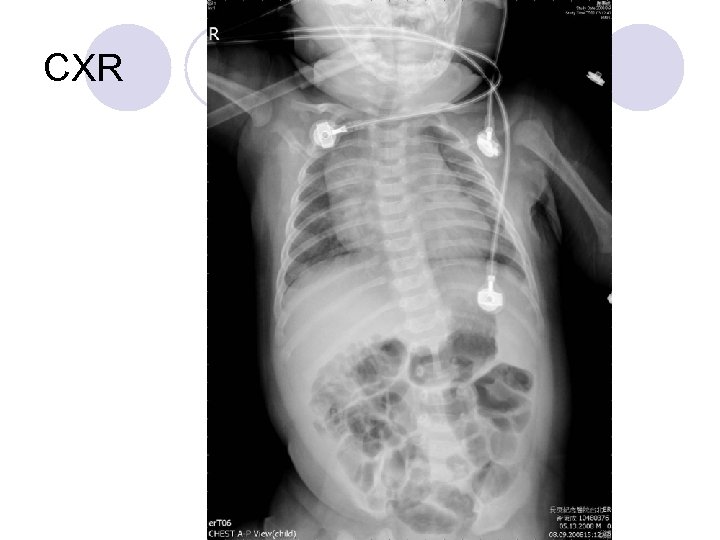

CXR